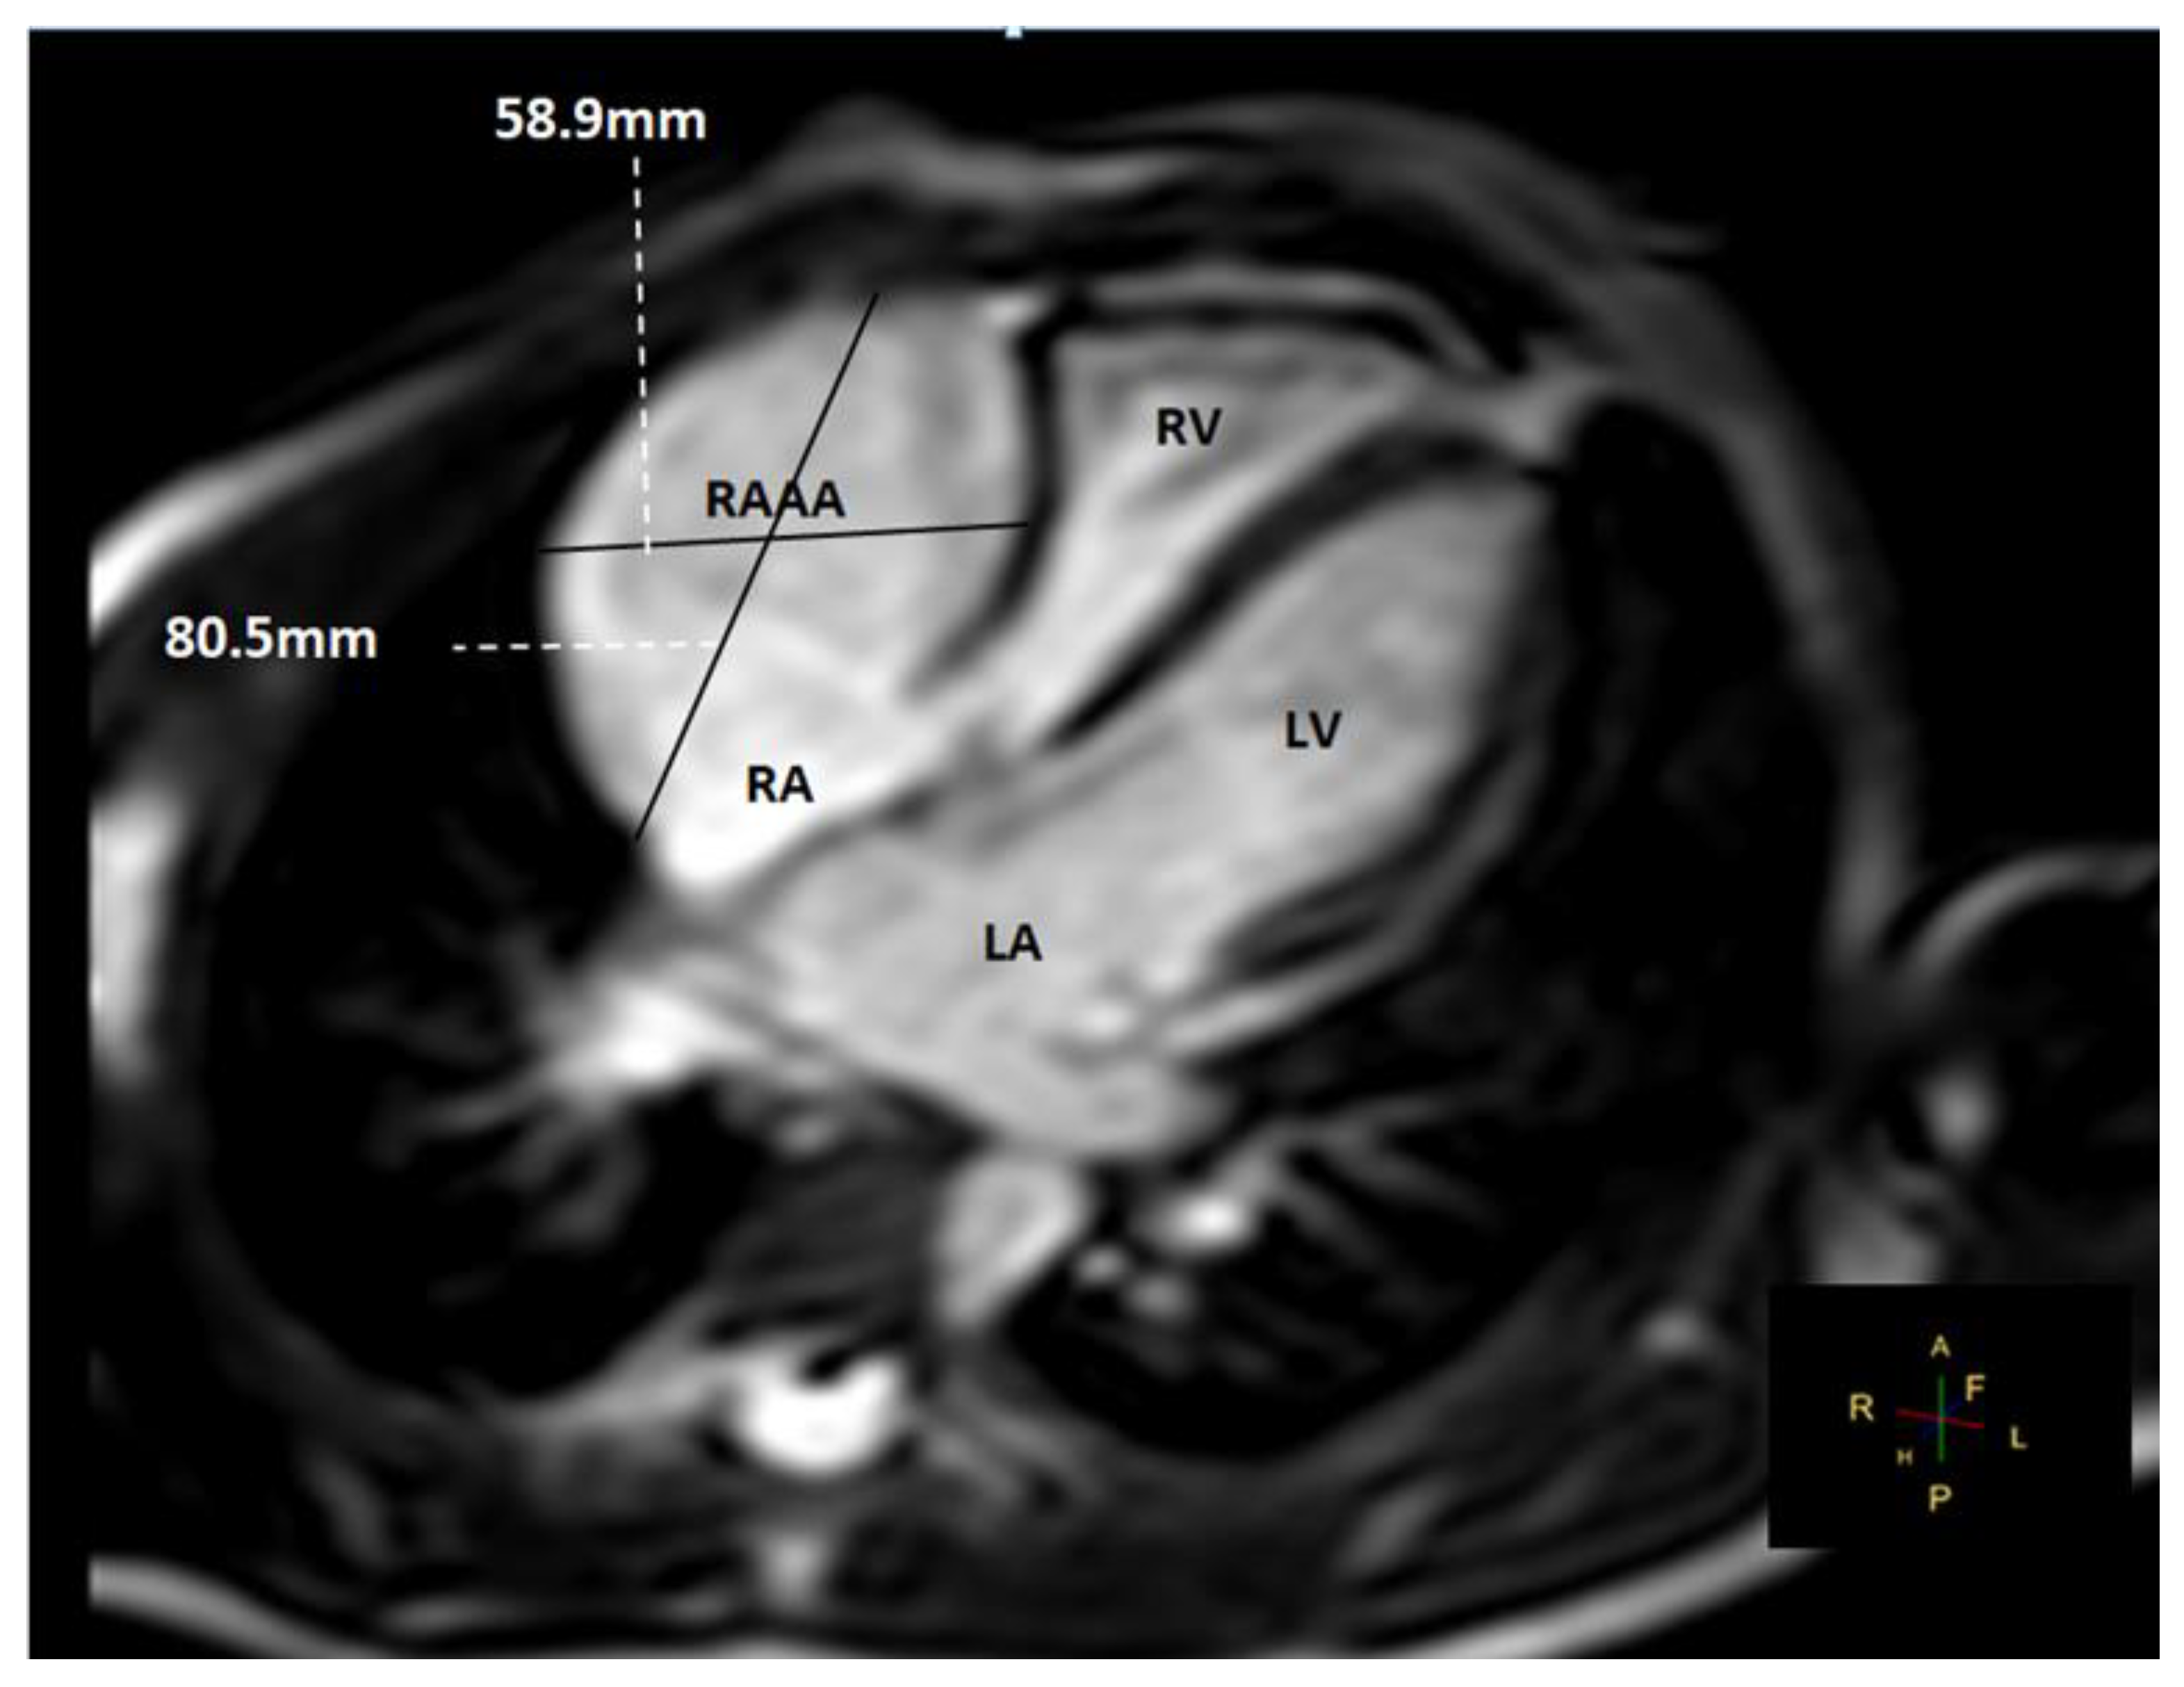

- MRI provides useful information regarding the cardiac structure, the thickness of the wall, and the route of the right coronary artery, as well as potential sites of compression.

| RAAA | Right Atrial Appendage Aneurysm |

| RAA | Right Atrial Appendage |

| RV | Right Ventricle |

| RA | Right Atrium |

| LV | Left Ventricle |

| LA | Left Atrium |